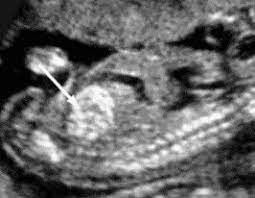

A Review On Techniques For Computer Aided Diagnosis Of Soft Markers For Detection Of Down Syndrome In Ultrasound Fetal Images Biomedical And Pharmacology Journal